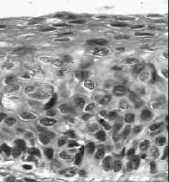

this is?

moderate dysplasia, CIN 2, p16 staining should be performed